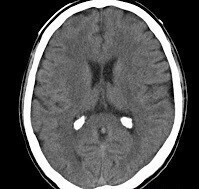

Une imagerie cérébrale est également réalisée aux urgences dont voici une coupe.

Figure 1.

L’imagerie cérébrale réalisée en urgence correspond à une tomodensitométrie cérébrale sans injection de produit de contraste iodé (pas de vaisseaux visibles) en coupe axiale.

L’hyperdensité intraventriculaire correspond à une banale calcification des plexus choroïdes classique pour l’âge.

L’imagerie ne retrouve donc aucune anomalie pouvant expliquer la symptomatologie du patient.